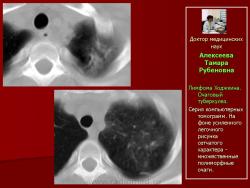

Рис.5.Б-ная А. Лимфома Ходжкина. Очаговый туберкулез.

Обзорные рентгенограммы с интервалом один месяц. В левом легком на фоне усиленного рисунка появились мелкие очаги уплотнения

Рис. 6. Та же б-ная А. Лимфома Ходжкина. Очаговый туберкулез.

Серия компьютерных томограмм. На фоне усиленного легочного рисунка сетчатого характера - множественные полиморфные очаги.